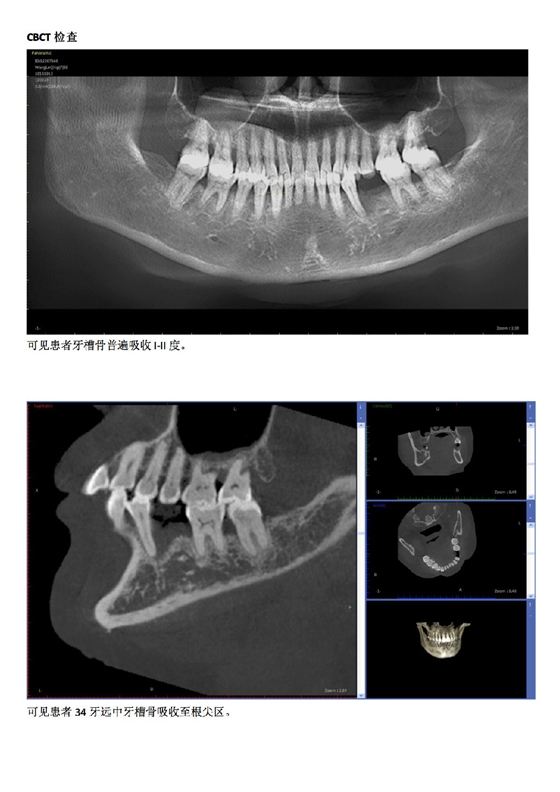

首頁牙周防治 牙周病患者種植治療+鄰牙GTR病例匯報(bào)

牙周病患者種植治療+鄰牙GTR病例匯報(bào)